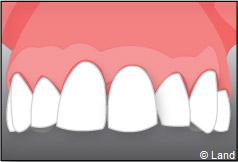

Exemple d’un implant unitaire pour remplacer une dent antérieure manquante.